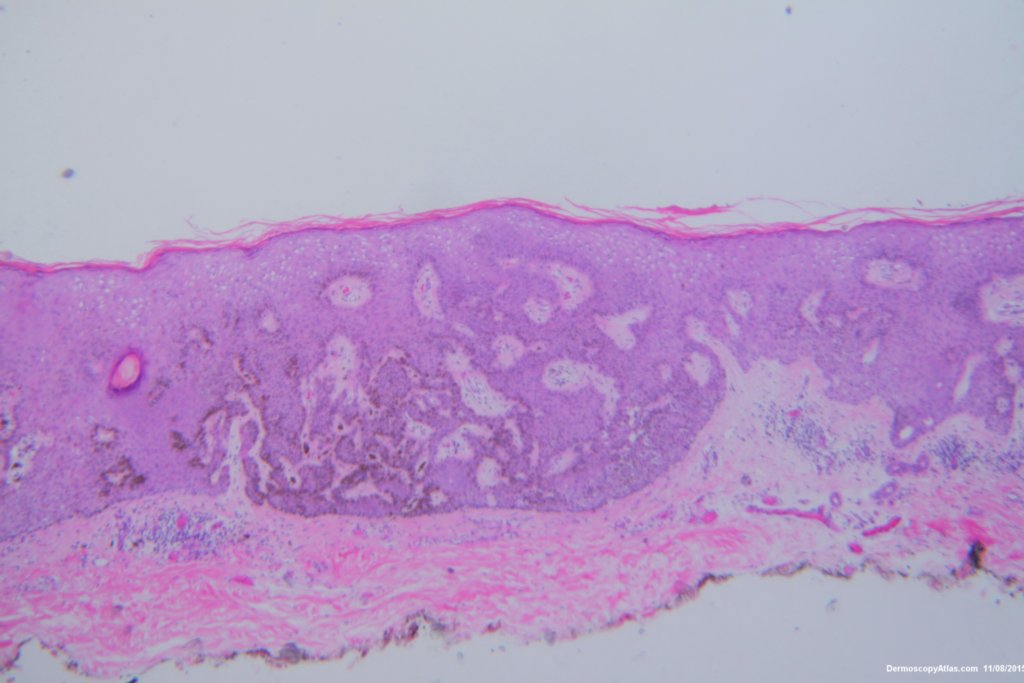

Diagnosis: Seborrhoeic keratosis irritated

This lesion looked darker than the many other seborrhoeic keratoses on this elderly man's back. It was thought there might be a lentiginous proliferation of atypical melanocytes in the lesion . Also the multiple colours and the white lines were unusual for a seborrhoeic keratosis. However pathology of a large shave biopsy excision showed only a pigmented thick seborrhoeic keratosis with increased pigment in normal basal keratinocytes. The blue colour was because of the depth of the lesion ie thick. No idea why the white lines!